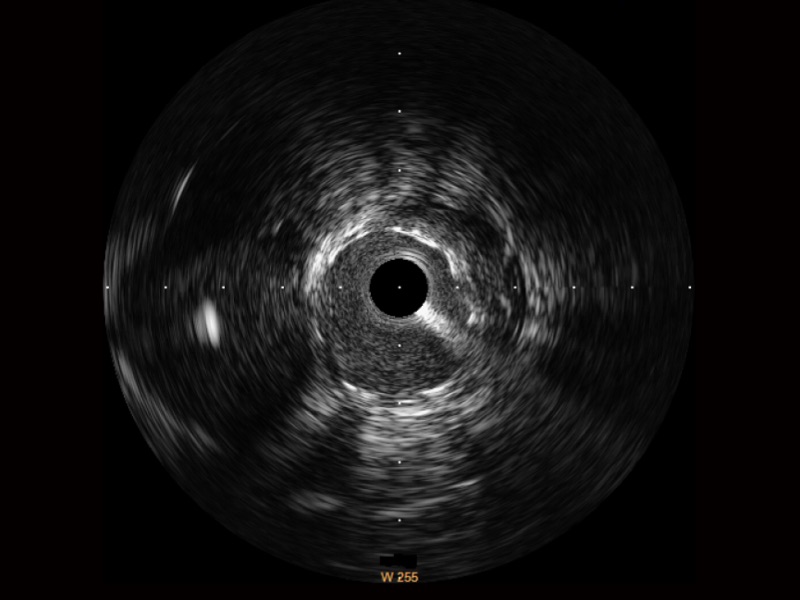

环球UG官网宽频IVUS图像

传统IVUS图像

对比传统IVUS导管成像,环球UG官网宽频IVUS图像的近场支架梁显影更细腻,远场中膜外血管仍清晰可辨,兼顾远中近,兼顾分辨力与穿透深度